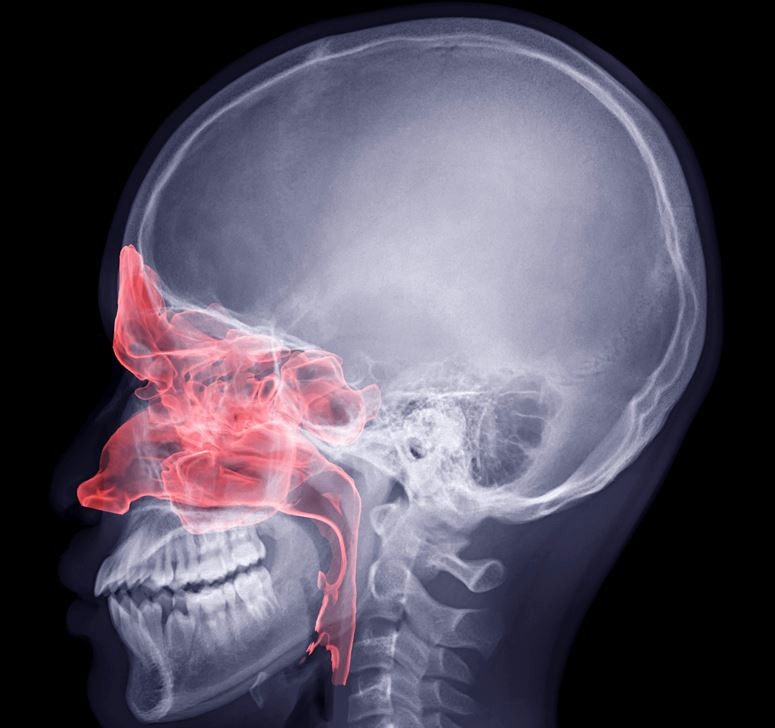

부비동은 눈과 코 주변의 얼굴뼈 속에 자리한 빈 공간으로, 상악동·사골동·전두동·접형동 네 부위로 나뉜다. 이곳은 공기를 데우고 습도를 조절하며, 목소리의 울림을 만드는 역할을 한다. 또한 외부의 온도 변화나 압력에 완충 작용을 해 머리의 무게를 줄여준다. 하지만 이 부비동에도 암이 생길 수 있다. 전체 두경부암 중 약 10% 정도를 차지하는 드문 질환이지만, 대부분이 상악동에서 발생한다.

부비동암을 진단하기 위해서는 코 내시경 검사와 CT, MRI 같은 영상검사가 먼저 시행된다. 종양이 뼈를 침범했는지, 안구나 뇌 주변으로 퍼졌는지를 확인하기 위해 정밀한 촬영이 필요하다. 이후 이상 부위에서 조직을 채취해 암세포 여부를 확진한다. 최근에는 PET-CT를 통해 암이 다른 부위로 전이됐는지까지 확인하는 경우도 많다.